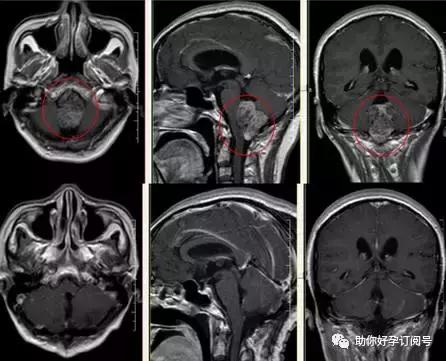

检查:颅内畸胎瘤影像学特征有其显著特点,能够作出初步诊断。

(4)MRI检查T1及T2像出现的信号极为混杂,但边界较清楚,呈结节状或分叶状,良性畸胎瘤边界无水肿(T2像显示清楚的高信号),如有周边水肿,提示肿瘤为恶变成分或恶性畸胎瘤,肿瘤在注药后瘤壁和实质部分明显强化。